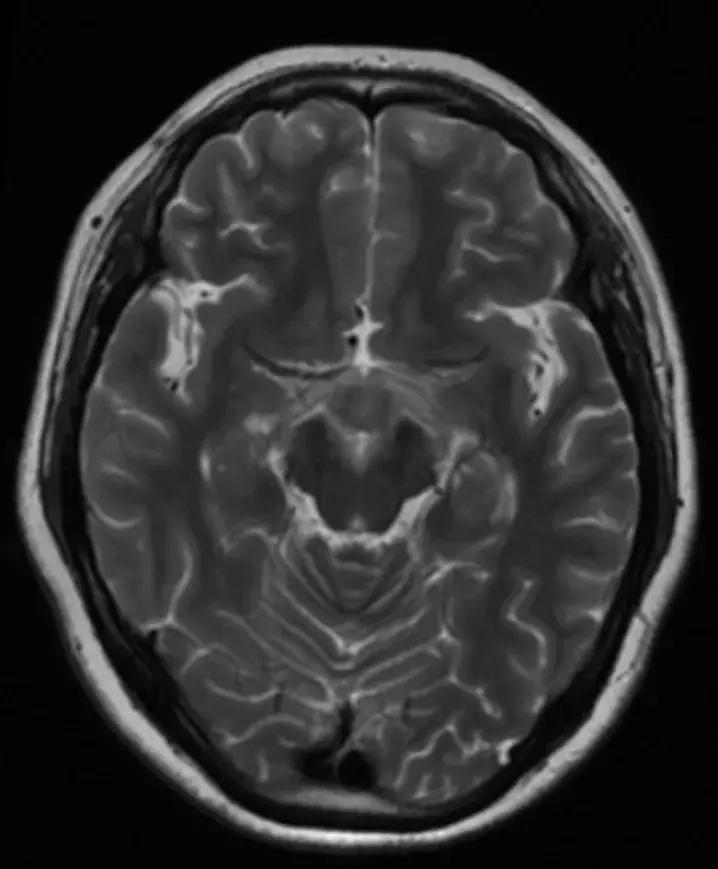

下丘脑见一类圆形异常信号灶,大小约1.6×1.4cm,T2WI呈等略高信号,T1WI呈等信号,DWI呈等信号,增强后明显异常强化,轻度压迫视交叉,FLAR见视交叉及双侧后方视束信号增高。